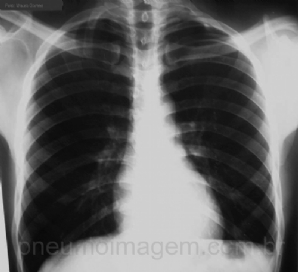

CASO CLÍNICO #9

Paciente do sexo feminino, 87 anos, apresenta tosse crônica, síndrome consumptiva e queda do estado geral. Nega febre e dispneia. Qual a sua hipótese diagnóstica? Deixe os seus comentários abaixo! ***** Female patient, 87 years old, has chronic cough, wa...